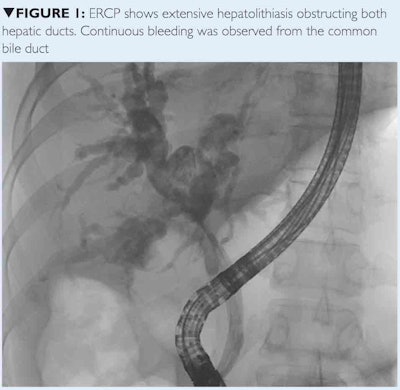

The patient first underwent an endoscopic retrograde cholangiopancreatogram (ERCP) with placement of two biliary stents. After initially improving for a few days, the patient developed hematemesis and the pain recurred. A second ERCP again showed extensive hepatolithiasis in both liver lobes obstructing both hepatic ducts, and active bleeding was observed from the common bile duct. Four units of packed red blood cells were transfused to the patient (figure 1).